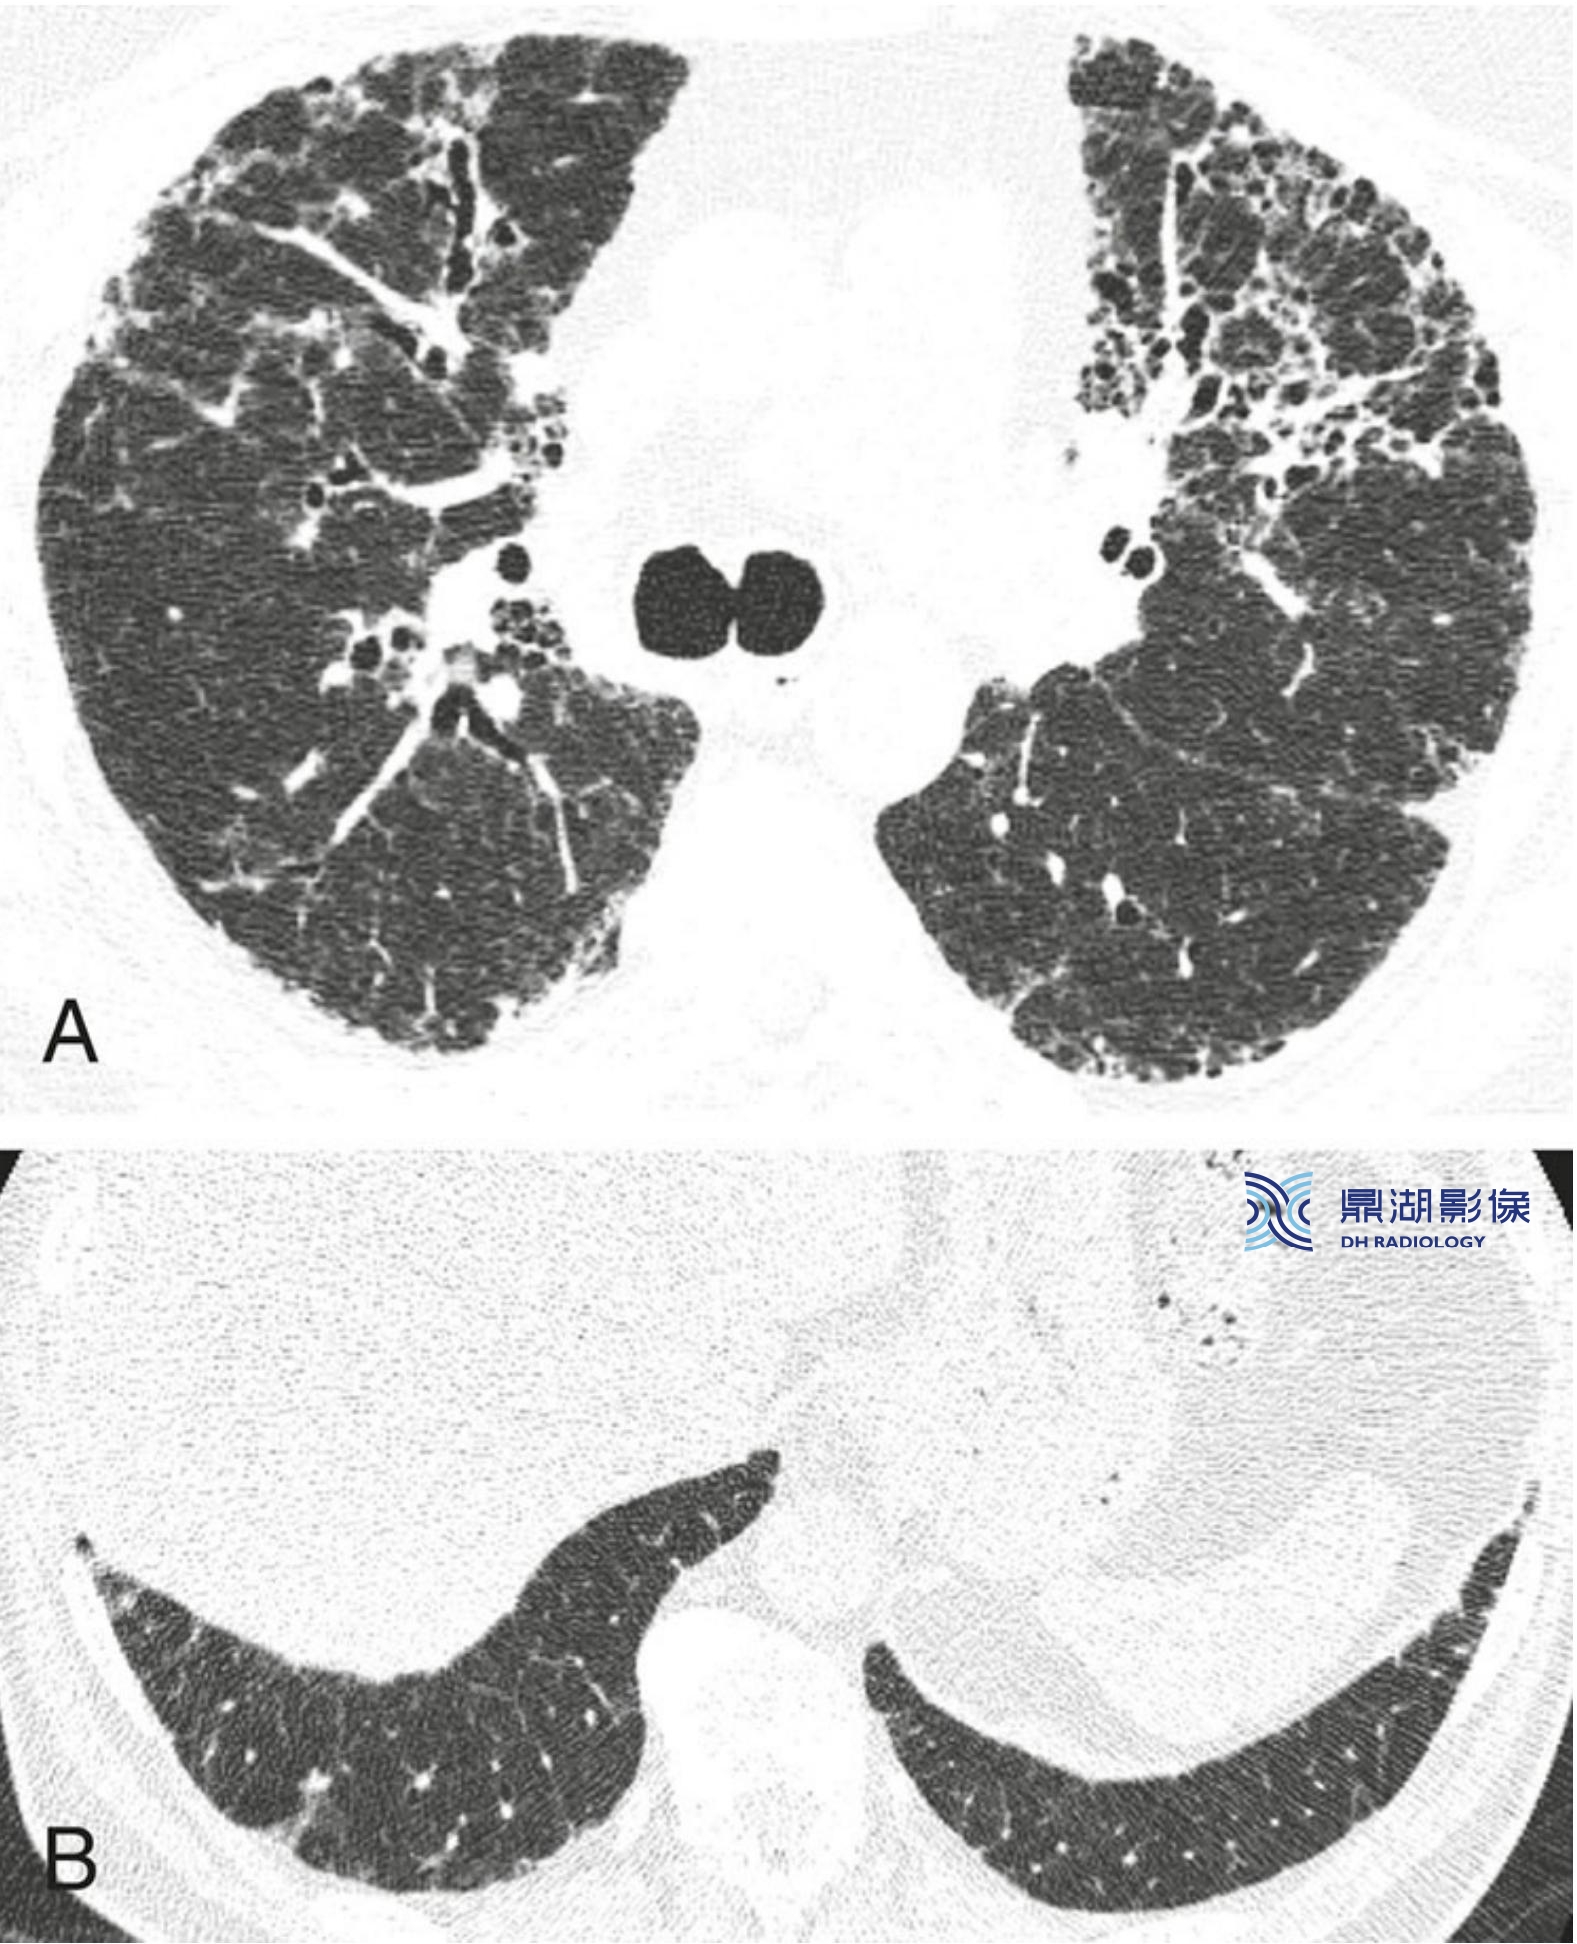

特发性肺间质纤维化(IPF),不典型分布。

该IPF患者经肺活检证实为普通型间质性肺炎(UIP),其不典型表现为纤维化不以胸膜下分布为主而是明显累及肺中央区(A)。

另外,肋膈角相对不受累(B)。IPF的不典型征象不少见。从HRCT表现上看,本例可能被认为与UIP “相悖”。

88af05edaac2a8a6b3a47e46d1ed6fd6.jpg特发性肺间质纤维化(IPF),不典型分布。